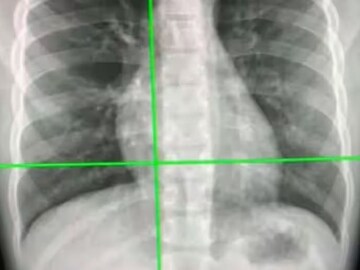

New COVID19 Test: এখন বুকের X-ray দিয়ে কোভিড পরীক্ষা! নতুন ব্যবস্থায় ৯০ শতাংশ কার্যকরীতা

এই পরিস্থিতিতে কোভিড নির্ণয় খুবই গুরুত্বপূর্ণ, চিকিৎসা এবং সংক্রমণ রোধের ক্ষেত্রে। অস্ট্রেলিয়ান গবেষকরা সম্প্রতি দাবি করেছেন, একটি AI সিস্টেম তাঁরা তৈরি করেছেন যা, ৯৮ শতাংশের বেশি সঠিক ভাবে বুকের এক্স-রে থেকে কোভিড-১৯ সনাক্ত করতে পারে। এই পরীক্ষাই সর্বাধিক দ্রুত বলে দাবি।

এখন যে পদ্ধতিতে কোভিড-১৯ পরীক্ষা করা হয়, সেটি হল RT-PCR পরীক্ষা। তার চেয়ে এই এক্স-রে পরীক্ষা বেশি কার্যকরী হতে চলেছে বলে জানা গিয়েছে। ইউনিভার্সিটি অফ টেকনোলজি সিডনি (UTS), ডেটা সায়েন্স ইনস্টিটিউটের অধ্যাপক আমির এইচ গ্যান্ডোমির মতে, ‘বহুল ব্যবহৃত কোভিড-১৯ পরীক্ষা, রিয়েল-টাইম পলিমারেজ চেইন রিঅ্যাকশন (পিসিআর), ধীর এবং ব্যয়বহুল হতে পারে। অনেক সময় সঠিক ফলও পাওয়া যায় না। সেজন্যই রেডিওলজিস্টদের ম্যানুয়ালি সিটি স্ক্যান বা এক্স-রে পরীক্ষা করতে হবে, যা সময়সাপেক্ষ এবং ত্রুটির প্রবণ হতে পারে। কিন্তু নতুন AI সিস্টেমটি খুবই কার্যকরী। বিশেষত সেই সব দেশে যেখানে কোভিড-১৯-সংক্রমণ বেশি এবং রেডিওলজিস্টের অভাব রয়েছে।’

বুকের এক্স-রে বহনযোগ্য, সর্বত্রই পাওয়া যায় এবং সিটি স্ক্যানের তুলনায় আয়নাইজিং বিকিরণের এক্সপোজারও কম। ফলে এটা খুবই উপকারী হতে চলেছে বলে দাবি গ্যান্ডোমির।

সায়েন্টিফিক রিপোর্ট জার্নালে প্রকাশিত গবেষণাপত্রে জানান হয়েছে, কাস্টম কনভোল্যুশনাল নিউরাল নেটওয়ার্ক (Custom-CNN) নামক একটি ডিপ লার্নিং অ্যালগরিদম ব্যবহার করা হয়েছে এই সিস্টেমের জন্য।

অধ্যাপক গ্যান্ডোমি বলেন, ‘ডিপ লার্নিং একটি এন্ড-টু-এন্ড সমাধান দিতে পারে। যদি একটি PCR পরীক্ষা বা রাপিড অ্যান্টিজেন পরীক্ষায় নেতিবাচক বা অনিশ্চিত ফলাফল দেখায়, তাহলে রোগীদের ভাইরাসের উপস্থিতি নিশ্চিত করতে রেডিওলজিক্যাল ইমেজিংয়ের প্রয়োজন হতে পারে। সেই ক্ষেত্রে নতুন AI সিস্টেম উপকারী হতে পারে।’

তুলনামূলক বিশ্লেষণের মাধ্যমে Custom-CNN মডেলটির কার্যক্ষমতা মূল্যায়ন করা হয়েছিল। দেখা গেছে, নতুন মডেলটি অন্য AI ডায়াগনস্টিক মডেলের থেকে অনেক ভাল কাজ করেছে।